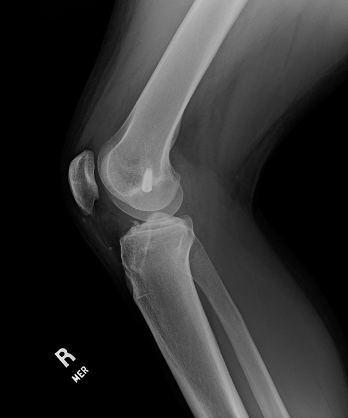

COLORADO SPRINGS, Colo. — Nearly half of patients with a first-time patellar dislocation and most patients with recurrent patellar dislocations underwent operative management, according to results presented at #AOSSM2022.